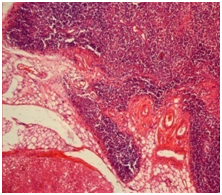

The thymus of rats of experimental group was presented in slices of various sizes with preserved division into cortex and medullary substance. Cortex and medullary substance contained a large number of lymphocytes in the state of destruction (with a modified form of vacuoles in the cytoplasm, karyopyknosis or karyolysis) between of which there were apoptotic bodies and cell fragments. In sporadic visual fields of the cortical substance there were defined focuses of necrosis, and of medulla - the devastation with the formation of fields which are consisting of epithelial reticular cells of changed shape, with irregularly shaped nuclei and pathological inclusions in the cytoplasm of eosinophilic color, petechial hemorrhages and orientation of lymphocytes around the extended full-blooded venous vessels. In one case one of the segments of the thymus of experimental animals was presented in a medium-sized slice with the absence of division into cortex and medullary substance, focal accumulations of haemosiderin in the parenchyma and extended lymphatic sinuses that were containing red blood cells and the cells that were in a state of destruction. In the arteries of the thymus (of the interlobular and parenchyma) there was detected intravascular hemolysis of erythrocytes with irregular thickening, dissection and focal destruction of the endothelium (Figure 4). In sporadic visual fields of interlobular spaces there were infiltrated with leucocytes.

Figure 4 Thymus, the experimental group, 1 day of the experiment. Hematoxylin and eosin × 200.

In the interlobular arteries has revealed intravascular hemolysis of erythrocytes with irregular thickening, dissection of wall and focal destruction of the endothelium.